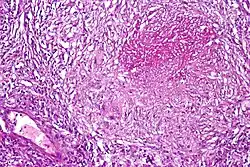

Pulmonary tuberculosis featuring necrotizing granulomas, H&E stain. -

Pulmonary tuberculosis featuring necrotizing granulomas, high power view, H&E stain. -